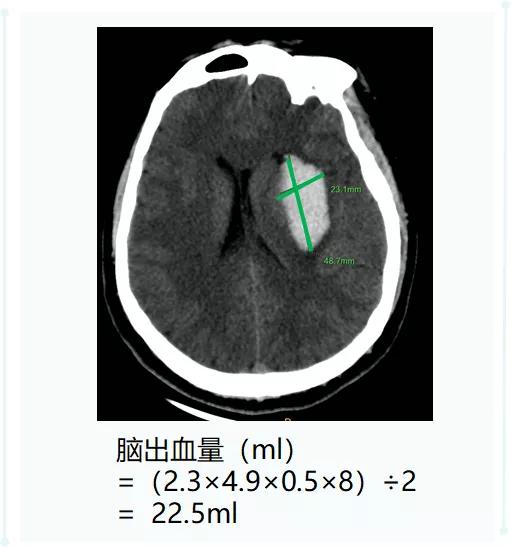

脑出血量 (ml)=

(最大层面的长×宽×层厚×层数)÷2

长、宽、层厚的单位:厘米